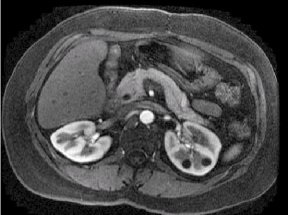

| Number | Description |

|---|---|

| 1 | out-of-phase |

| 2 | in-phase |

| 3 | water only |

Image Annotation

M3D/LAVA/flip angle: Water and Fat images are synthesized from collected in-phase and out-of-phase images; thus TE values for Water and Fat images are the average of IN-phase and Out-of-Phase TEs. In-phase and out-of-phase gets annotated according to the TE and TE2 values on screen.